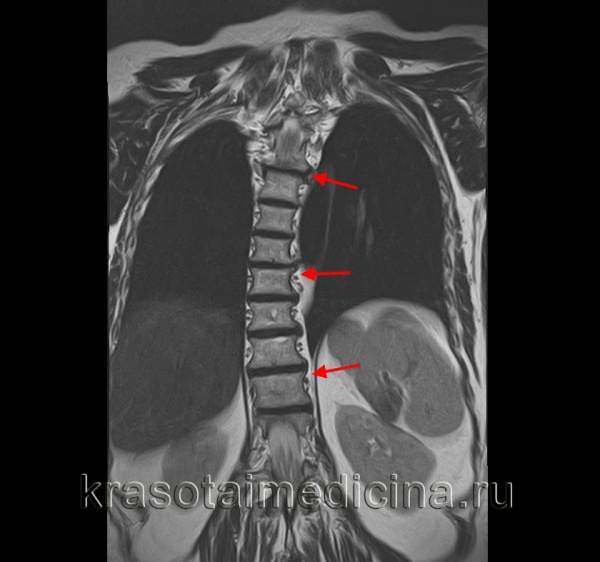

4. МРТ:

• Позволяет выявить аномалии позвоночника и спинного мозга, кистозные изменения, опухолевое и инфекционное поражение

о Многоплоскостная МРТ для выявления патологии позвоночника и спинного мозга:

- Фронтальные и аксиальные изображения в Т1 - и Т2-режимах

- Визуализация краниоцервикального сочленения

- Аксиальные Т2-ВИ подозрительных на наличие патологии зон

- Аксиальные Т2-ВИ конуса спинного мозга

• МРТ применяется в ходе предоперационного планирования для оценки дегенеративных изменений и выраженного центрального и/или фораминального стеноза позвоночника

• Артефакты магнитной восприимчивости на фоне металлоконструкций могут значительно ограничивать информативность исследования в отношении оценки состояния содержимого дурального мешка и межпозвонковых отверстий

• Эффективна в послеоперационном периоде в отношении выявления заполненных жидкостным содержимым полостей